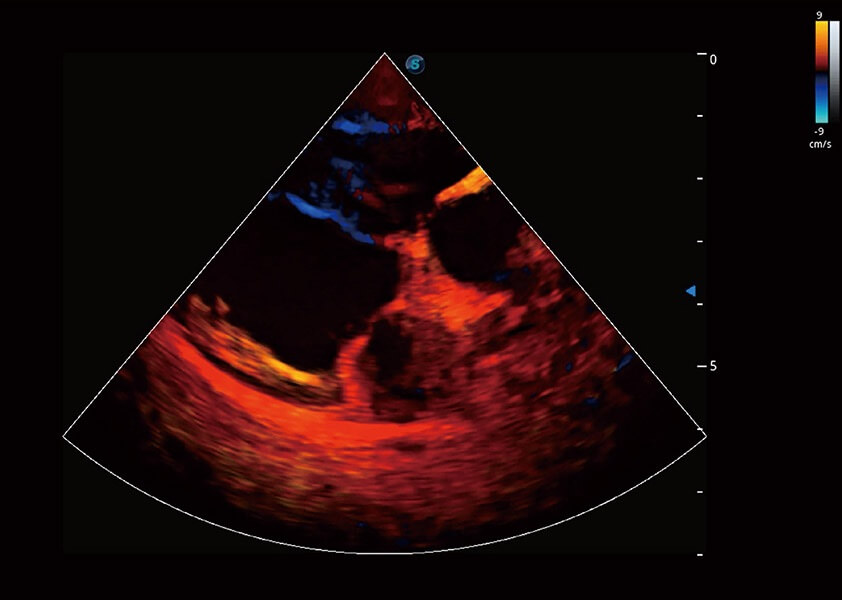

ProPet 60 作为一款高端台式动物超声设备,为动物医生的日常诊断提供了一系列贴合动物临床需求、解决临床实际问题的高级成像功能。凭借全系列高清探头,满足医生对腹部、心脏、生殖、浅表、肌骨等成像的所有需求,切实帮助您提升检查效率,提高诊断信心。

兽用彩色多普勒超声诊断系统

动物是人类最亲密的朋友和最值得信赖的伙伴。新葡的京集团8814检测站也一直致力于探索动物专用的超声影像解决方案。 全新推出的ProPet系列,是新葡的京集团8814检测站在动物超声影像智能化、专业化、精准化的一次跨越式革新。动物不能用言语来表述自己的不适,通过超声影像,ProPet系列搭建了动物医生与不同物种沟通的“桥梁”,为动物医生注入了“治愈之力”。